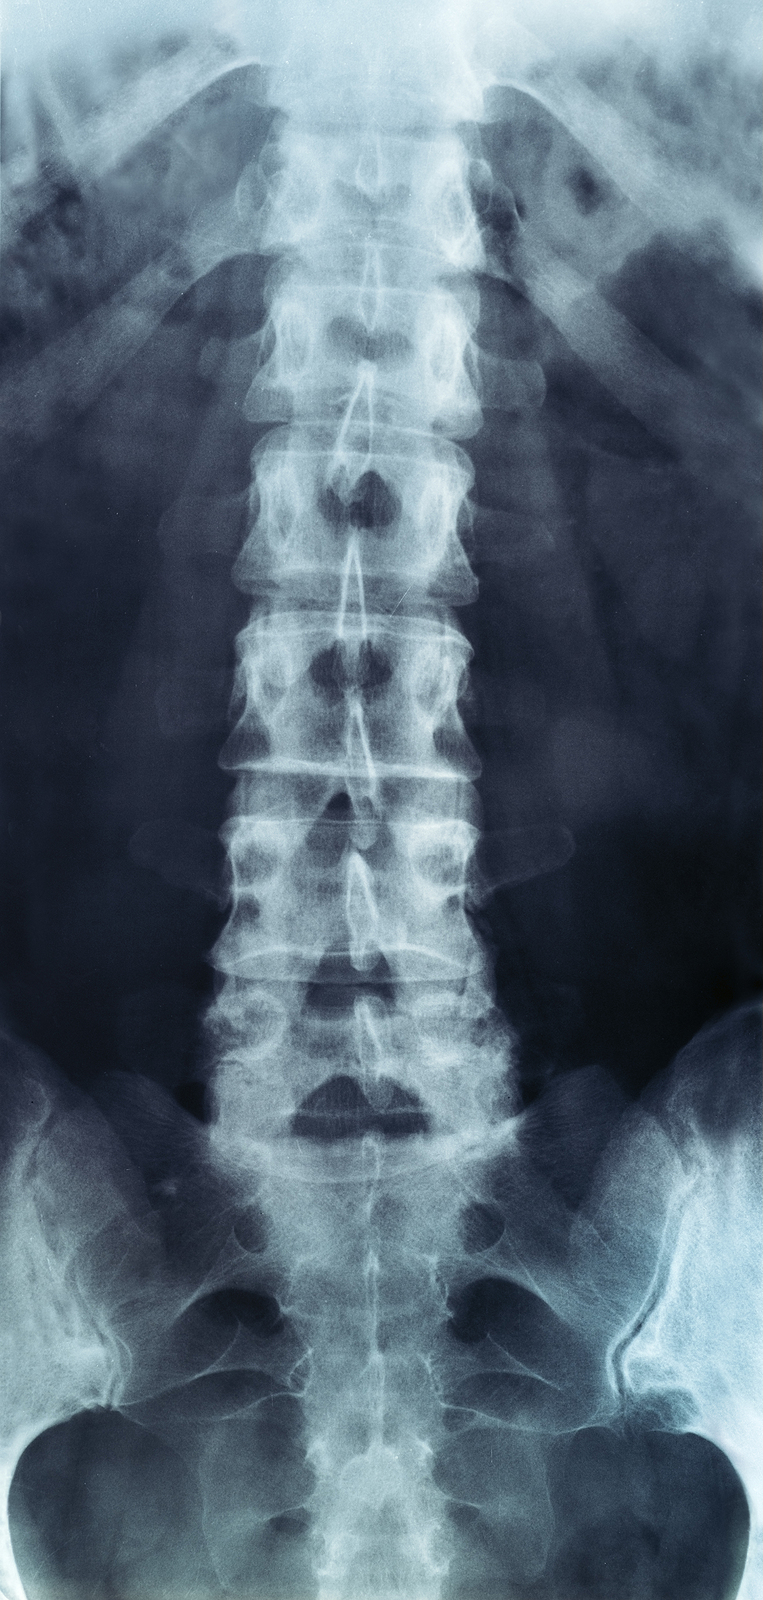

X-rays

X-rays are usually the first test ordered before any of the more specialized tests are completed. X-rays use electromagnetic radiation to show problems with bones and can also reveal problems such as fractures, infections, or bone tumors. X-rays of the spine can give your doctor information about bone alignment and can demonstrate how much degeneration has occurred in the spine. Both alignment and degeneration can affect the amount of space in the neural foramina and between the discs, which subsequently impacts the nerves in the area. This is important information your health care professional can use to establish a treatment plan.

Flexion and Extension X-rays

Special x-rays called flexion and extension x-rays may help to determine if there is true instability between vertebrae. These x-rays are taken from the side as you bend as far forward and then as far backward as you can. Comparing the two x-rays allows the doctor to see how much motion occurs between each spinal segment.